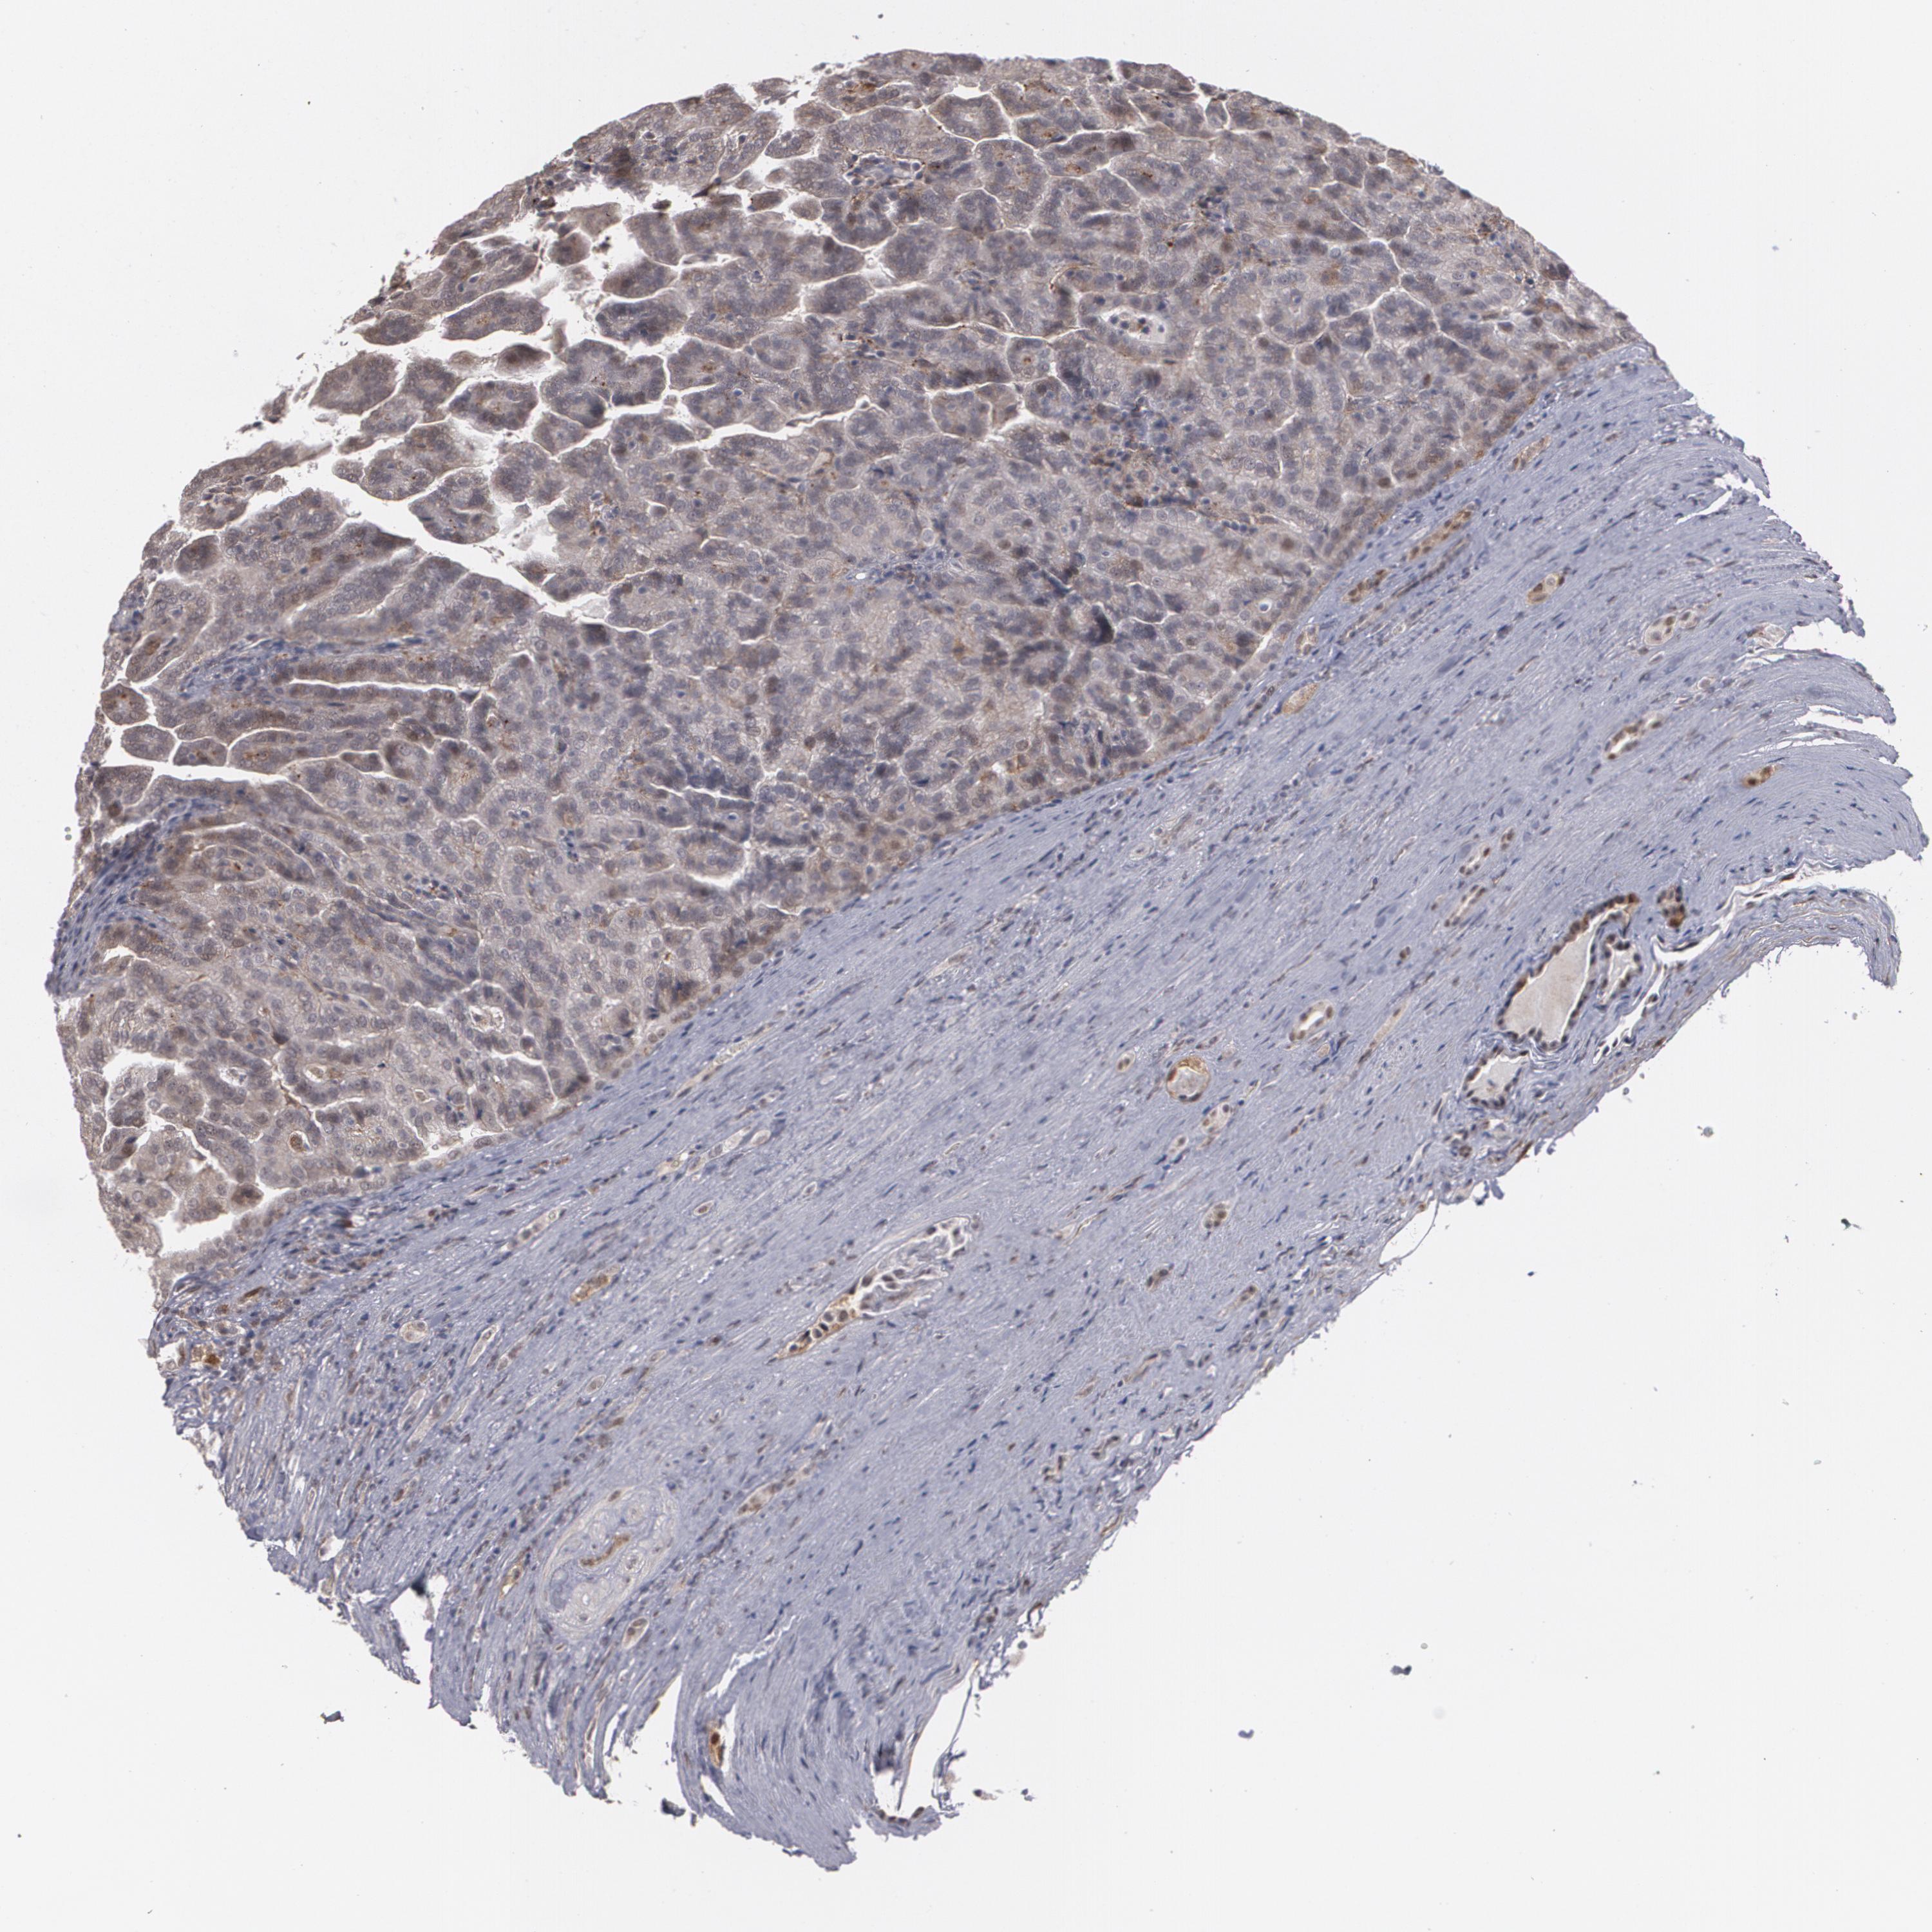

KIDNEY RENAL CLEAR CELL CARCINOMA (VALIDATION) - Interactive survival scatter ploti

The Survival Scatter plot shows the clinical status (i.e. dead or alive) for all individuals in the patient cohort, based on the same data that underlies the corresponding Kaplan-Meier plots. Patients that are alive at last time for follow-up are shown in blue and patients who have died during the study are shown in red.

The x-axis shows the expression levels (FPKM) of the investigated gene in the tumor tissue at the time of diagnosis. The y-axis shows the follow-up time after diagnosis (years). Both axes are complimented with kernel density curves demonstrating the data density over the axes. The top density plot shows the expression levels (FPKM) distribution among dead (red) and alive patients (blue). The right density plot shows the data density of the survived years of dead patients with high and low expression levels respectively, stratified using the cutoff indicated by the vertical dashed line through the Survival Scatter plot. This cutoff is automatically defined based on the FPKM cutoff that minimizes the p-score. The cutoff can be changed by dragging the vertical line or by entering a cutoff value in the square labeled "Current cut-off".

Under the Survival Scatter plot the p-score landscape (black curve; left axis) is shown together with dead median separation (red curve; right axis). Dead median separation is the difference in median mRNA expression between patients who have died with high and low expression, respectively. It is calculated as follows: median FPKM expression of dead patients with high expression - median FPKM expression of dead patients with low expression. This is intended to aid the user in visually exploring custom cutoffs and the associated p-scores and dead median separation.

Individual patient data is displayed and can be filtered by clicking on one or more of the category buttons on the top of the page. Categories describing expression level and patient information include: high, low, alive, dead, female, male and tumor stages. The scale of the x-axis can be toggled between linear and log-scale by clicking on the "x log" button. Mouse-over function shows TCGA ID, patient information and mRNA expression (FPKM) for each patient.

& Survival analysisi

Kaplan-Meier plots summarize results from analysis of correlation between mRNA expression level and patient survival. Patients were divided based on level of expression into one of the two groups "low" (under cut off) or "high" (over cut off). X-axis shows time for survival (years) and y-axis shows the probability of survival, where 1.0 corresponds to 100 percent.

ZNF75A is potential prognostic, high expression is favorable in Kidney Renal Clear Cell Carcinoma (validation)

Best expression cut offi

Based on the FPKM value of each gene, patients were classified into two groups and association between prognosis (survival) and gene expression (FPKM) was examined. The best expression cut-off refers the FPKM value that yields maximal difference with regard to survival between the two groups at the lowest log-rank P-value. Best expression cut-off was selected based on survival analysis .

When clicking on this number, the vertical dashed line indicating cut-off, the interactive survival plot, and the Kaplan-Meier curve will be adjusted to show results based on the best expression cut-off.

: 7.27

Average pTPM 8.2

Number of samples 100